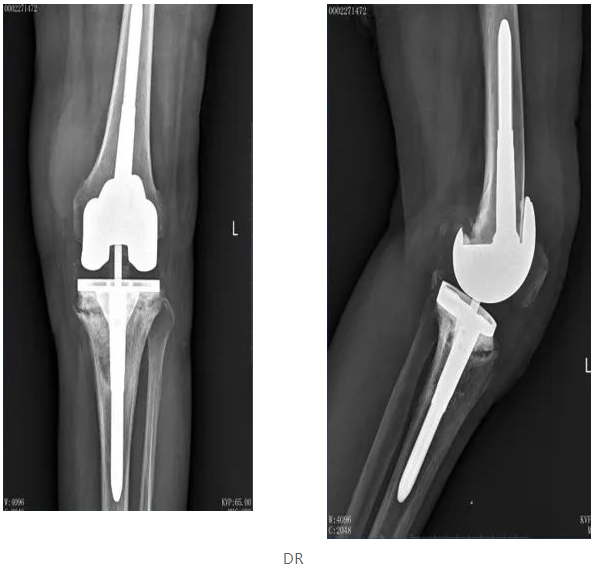

02 女,65岁,膝关节置换术后

1、确认无骨水泥假体的骨小梁生长情况

4、图像的空间分辨率高于CT图像